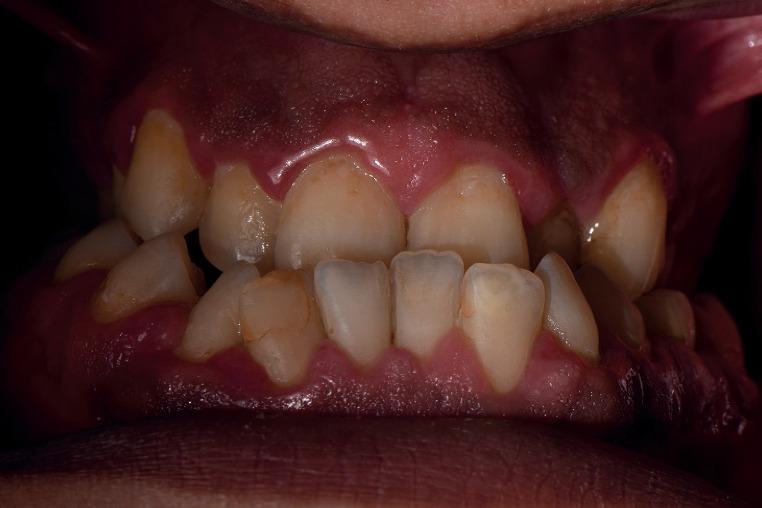

Radiculomegaly is a rare condition involving elongated tooth roots. This condition has significant clinical implications and has been associated with syndromes such as oculofaciocardiodental syndrome. However, only a few nonsyndromic cases of radiculomegaly have been reported. Here, we report a case of nonsyndromic radiculomegaly in a Saudi individual. A subsequent review of the literature suggests endodontic management modalities for individuals with the dental findings demonstrated in the present case.